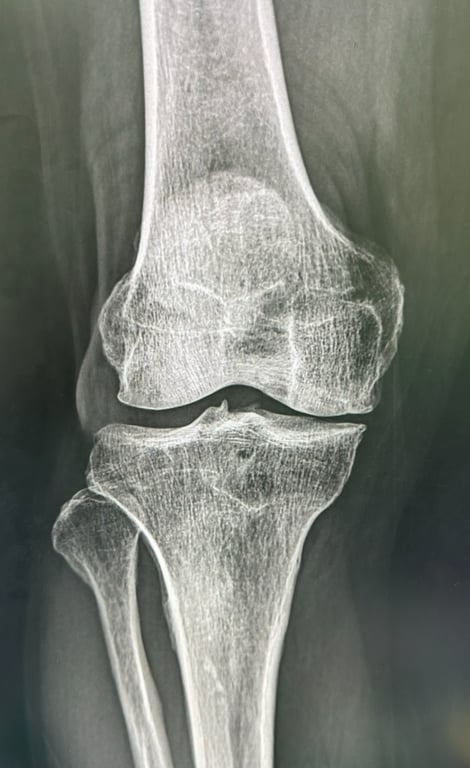

一期:輕微退化

輕微程度退化

關節軟骨開始出現輕微磨損,活動後可能感到不適,但休息後症狀會緩解

X光影像

主要症狀

運動或長時間活動後膝蓋輕微疼痛

休息後疼痛會完全消失

偶爾感到膝蓋緊繃或僵硬

治療建議

以生活方式調整和保守治療為主,重點在於預防進一步退化

醫師會透過詳細的病史詢問、膝關節的理學檢查(觸診、活動度測試)來初步評估。X光檢查是診斷退化性膝關節炎最主要的影像工具,可以清楚看到關節間隙變窄、骨刺形成、軟骨下骨硬化等退化徵象。